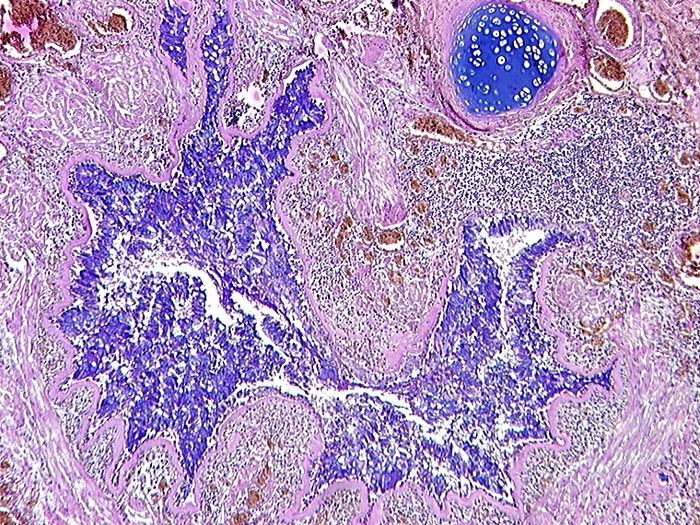

PathoPic ID 542 - Asthma bronchiale

Asthma bronchiale

Kleiner Bronchus mit Becherzellhyperplasie, starker Verdickung der Basalmembran und Hypertrophie der glatten Muskulatur. Sternförmiges Lumen.

Tod im Asthmaanfall bei bekanntem Asthma bronchiale.